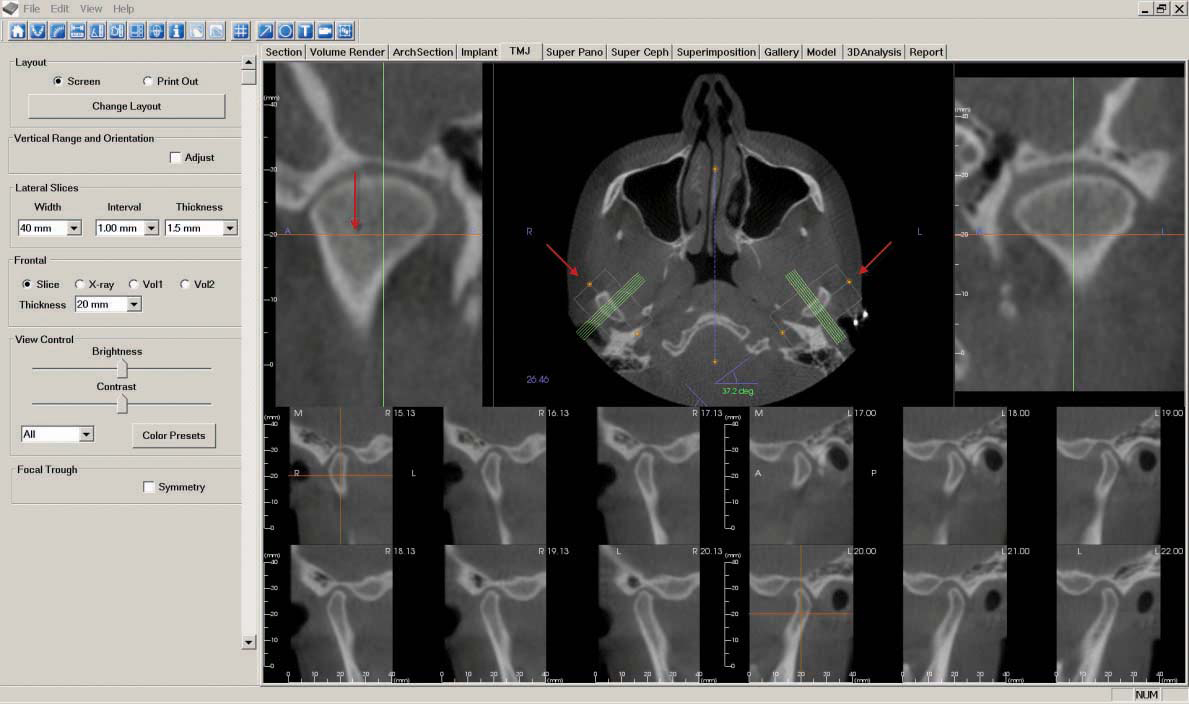

g. Next, go to the "TMJ" tab to create the "TMJ Coronal" image. First, move the orange line while focusing on the center image until the condyles (shaped like kidney beans) appear. Click on the white rectangle and position over each condyle, using the orange points to bisect the vertical center of the condyles. Rotate the boxes 90 degrees toward the midline to make coronal slices of the condyles. You can adjust the width and interval settings to ensure the slices match the size of the condyles.

As described in step 7, "Capture to Gallery" and select "Whole View" in the "Select Image to Capture" pop-up window. Click "OK," then name the image "TMJ Coronal."

h. The "TMJ" tab is also used to create the "TMJ Sagittal" image. Click on the white rectangle and position over each condyle, using the orange points to bisect the horizontal center of the condyles. Rotate the boxes toward the midline to bisect the condyle. Adjust the interval setting to view slices of the entire width of the condyles.

As described in step 7, "Capture to Gallery" and select "Whole View" in the "Select Image to Capture" pop-up window. Click "OK," then name the image "TMJ Sagittal."